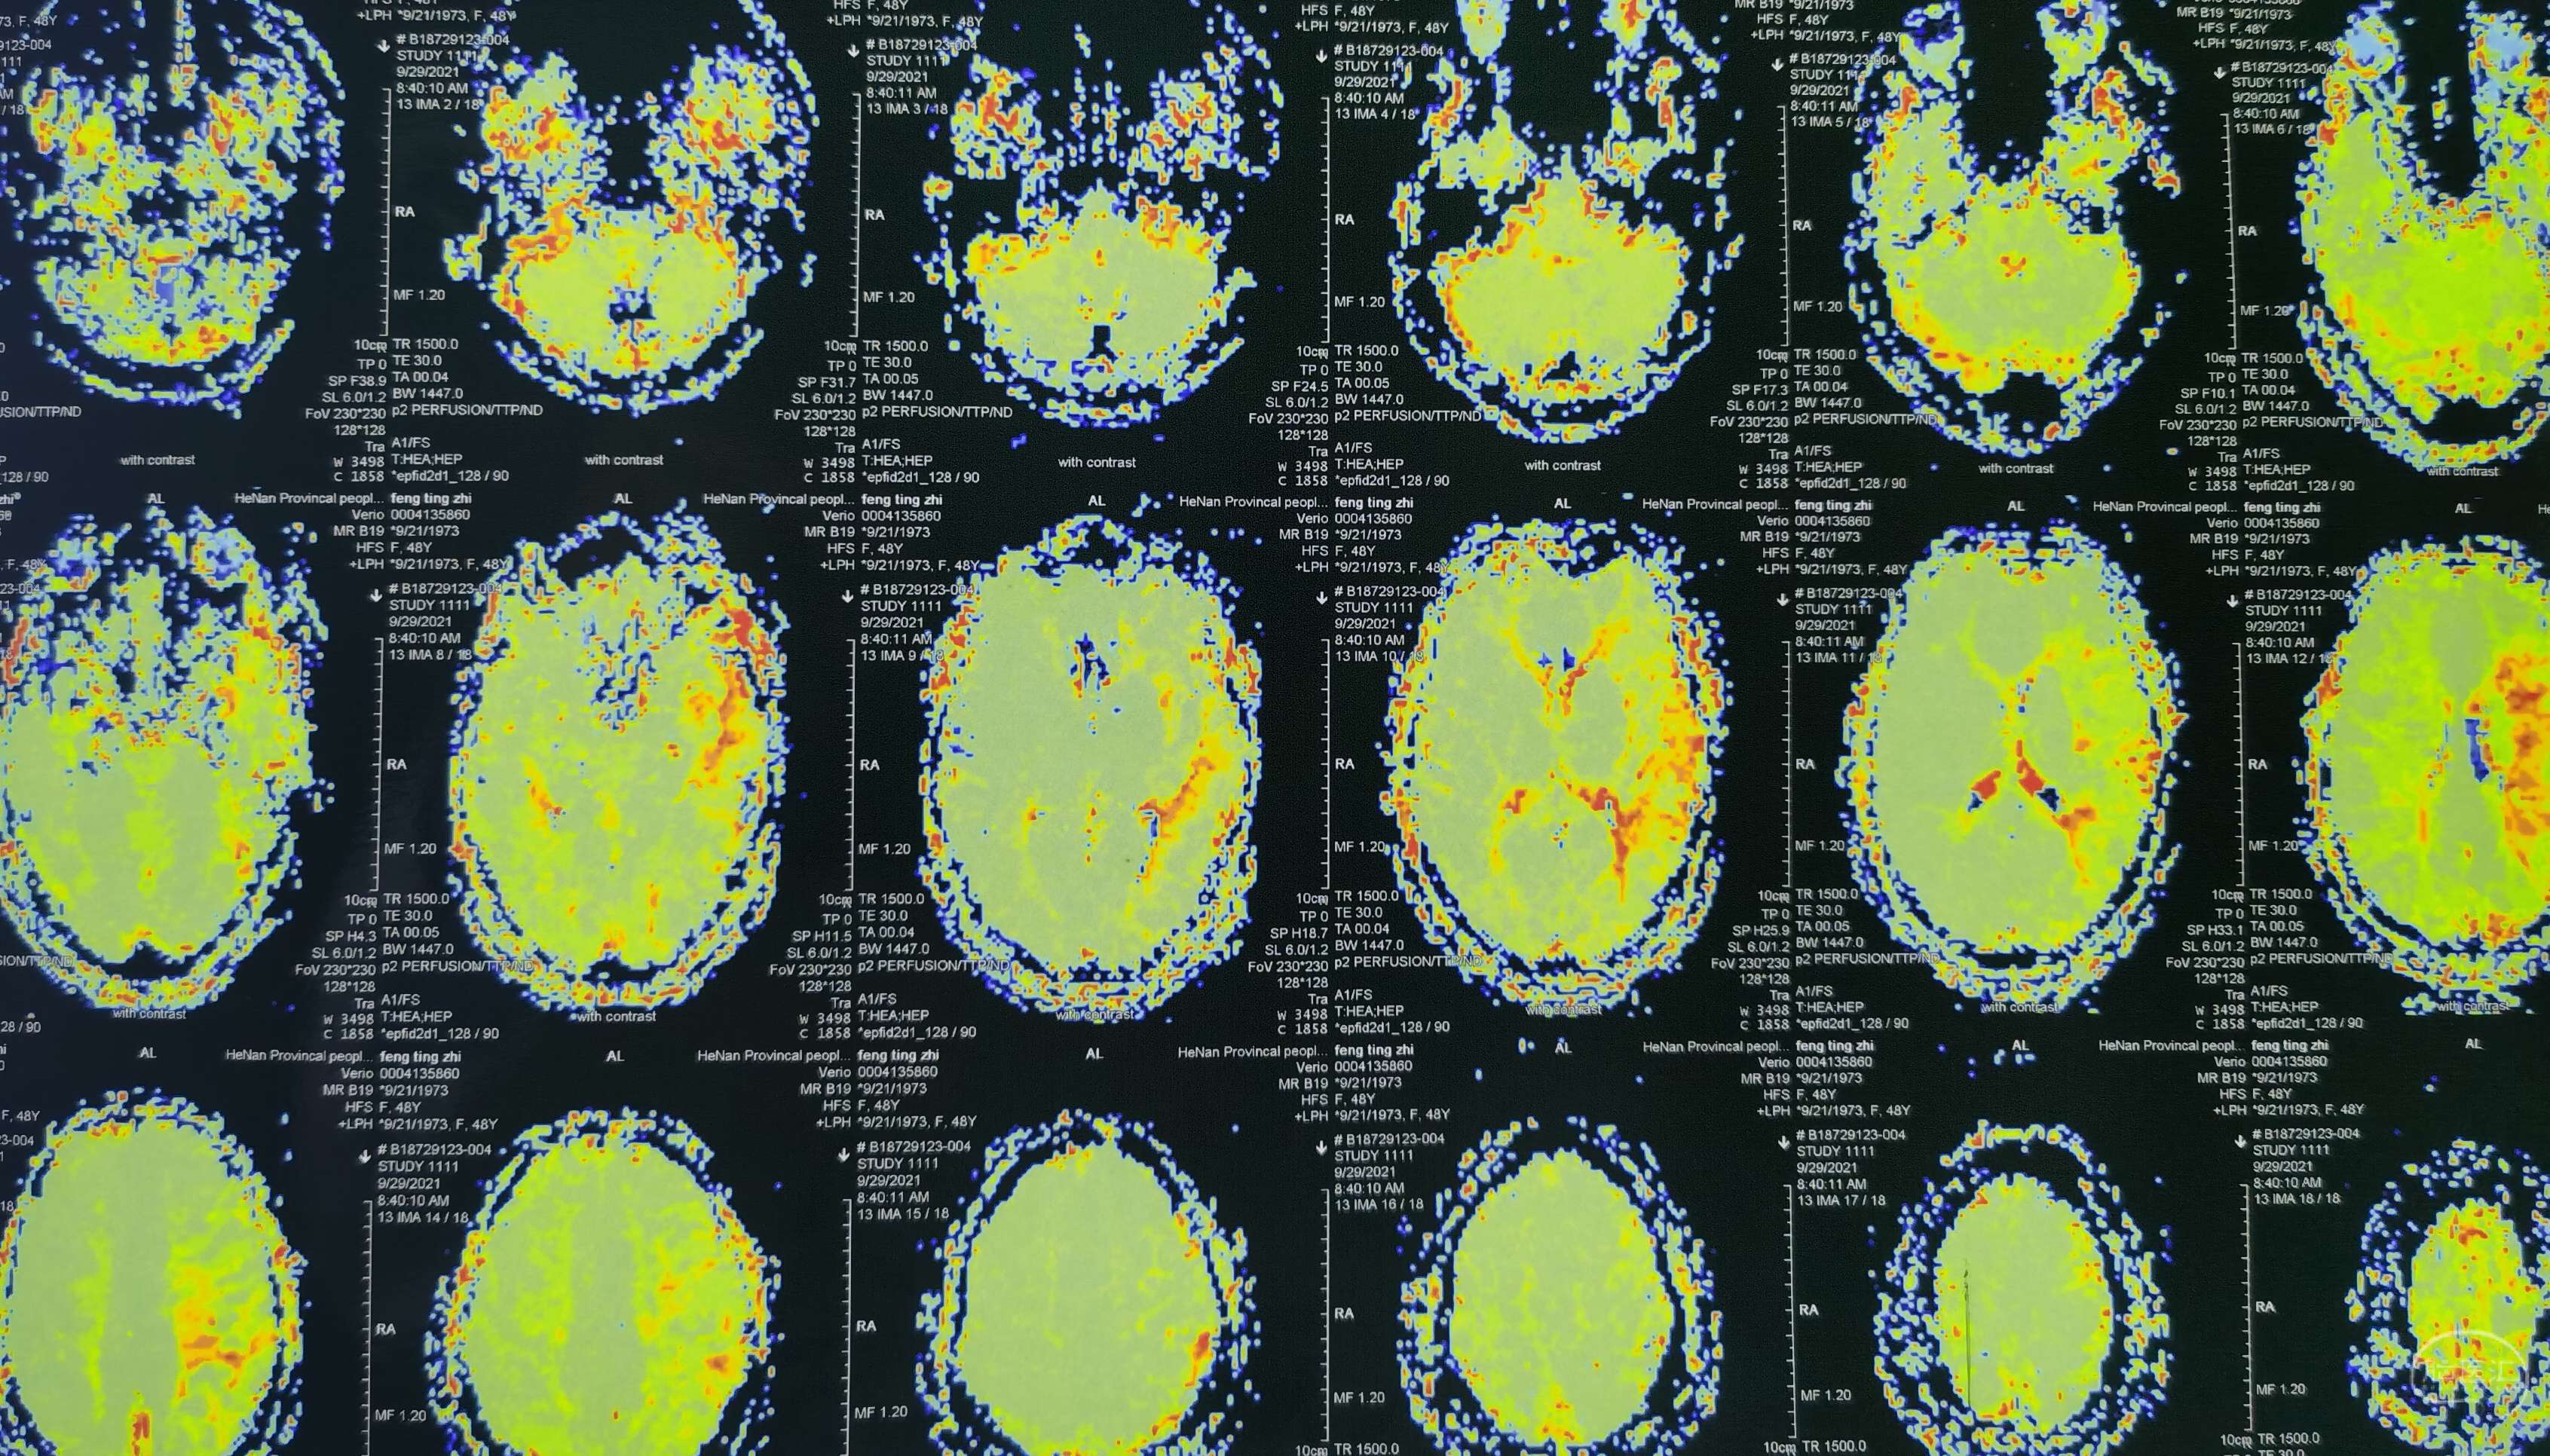

磁共振灌注提示:左侧大脑半球低灌注改变。

磁共振灌注提示:双侧大脑半球低灌注改变。